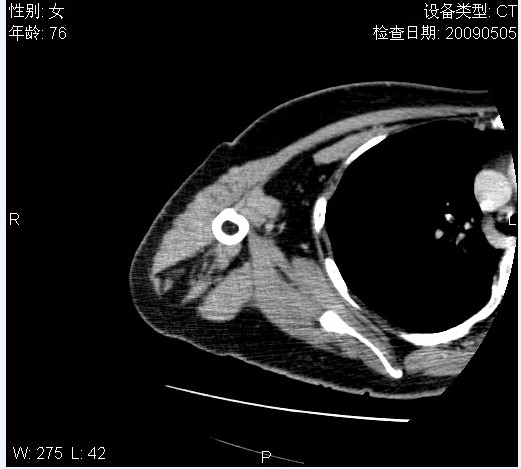

标题: CT19811:女,76岁,右上臂肿物1个月 [打印本页]

标题: CT19811:女,76岁,右上臂肿物1个月

使用了造影剂,可惜效果不太好

右肱骨上段软组织内见梭形低密度影,边界清楚,最长径约54mm.

病理结果:脂肪瘤。术中见肱骨骨膜受侵,有出血,量不详。

当时诊断意见:右肩三角肌内蔓状血管瘤(先天性动静脉瘘)。

本人对病理结果有个疑问:单纯的脂肪瘤内为什么有条状软组织影,那应该脂肪肉瘤才对啊?

该病例增强效果欠佳,由于经验欠缺,我们注射对比剂是由下肢足背静脉给药。注速2.0。虽然如此,但我们可以看到肿块内部条状软组织影是强化的,而且是连续的,并可见供血动脉是由腋动脉的其中一支即肩胛下动脉分出。从这些征象我们可以得出诊断:蔓状务血管瘤。

可病理偏偏为脂肪瘤,我怀疑取材有问题。因为蔓状血管瘤异常扩张的静脉外周是脂肪成分,它可以侵犯肌组织及骨骼。当取材于外周,那当然是脂肪瘤。此时我认为临床的最终诊断不应单从病理出发,应该综合考虑。